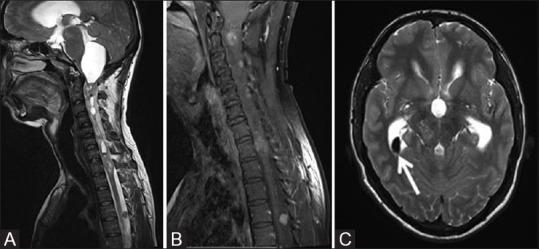

Phakomatoses or Neurocutaneous syndromes are a heterogeneous group of disorders and have variable inheritance pattern. Currently, more than 30 entities are included in this group. These disorders primarily affect the central nervous system; however, skin, viscera, and other connective tissues can also be involved with variable clinical presentation. We will describe and illustrate the various radiological findings of the common entities through the iconography of the cases presented to our department.

phakomatoses或神经皮肤综合征是一组异质性疾病,具有可变的遗传模式。目前,该组包括30多种疾病。这些疾病主要影响中枢神经系统;然而,皮肤、内脏和其他结缔组织也可能受累,临床表现各异。我们将通过提交至我科病例的影像学表现来描述和说明常见疾病的各种放射学表现。